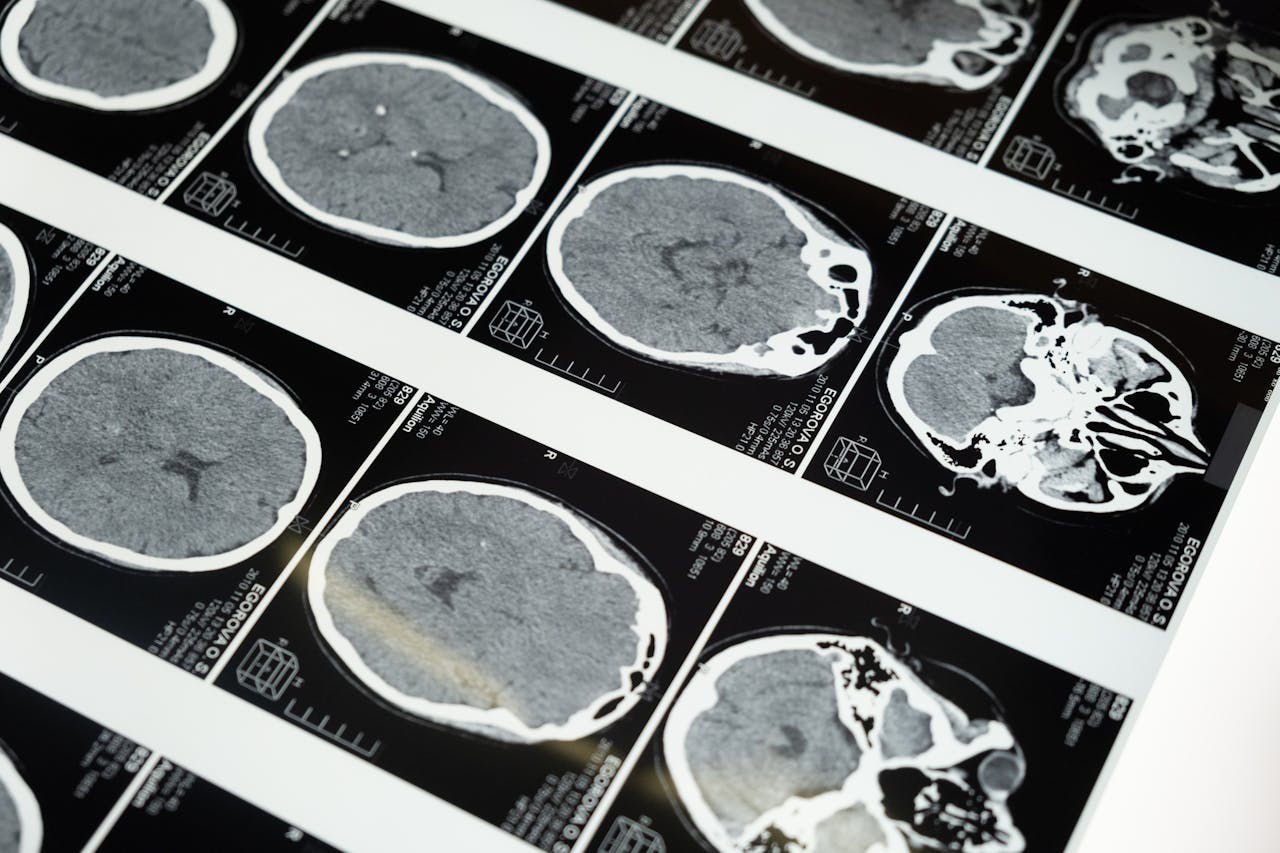

According to Tina, her son’s symptoms began gradually and then intensified within a few weeks. He started having trouble focusing his eyes and complained of double vision. There were also moments when he seemed off-balance, which led his parents to think it might be an ear infection or vertigo. Unfortunately, these were early indicators of something far more severe. After several medical consultations and scans, the diagnosis was revealed: Diffuse Intrinsic Pontine Glioma, commonly known as DIPG.

The news shattered the family. Doctors explained that DIPG was an extremely aggressive brain tumour that primarily affects children and that it had no cure. The tumour forms in the brain stem, the part that controls breathing, heart rate, and movement. Because of its location, it is impossible to remove surgically, leaving families like the Hubers with few options beyond limited radiation therapy.

Diffuse Intrinsic Pontine Glioma is considered one of the most devastating childhood cancers. According to experts, only a few hundred children worldwide are diagnosed each year, and survival rates remain tragically low. Because the tumour grows in the brain stem, it cannot be operated on without causing fatal damage. Even advanced treatments such as chemotherapy have limited effectiveness due to the blood-brain barrier, which prevents drugs from reaching the tumour cells.

Dr. Susan Chang, a neuro-oncologist at the University of California, explains that DIPG research has historically received less funding compared to more common cancers. However, cases like Brody’s have reignited public interest in improving treatment options. Experimental gene therapies and new radiation approaches are currently being studied, offering a glimmer of hope for future patients.